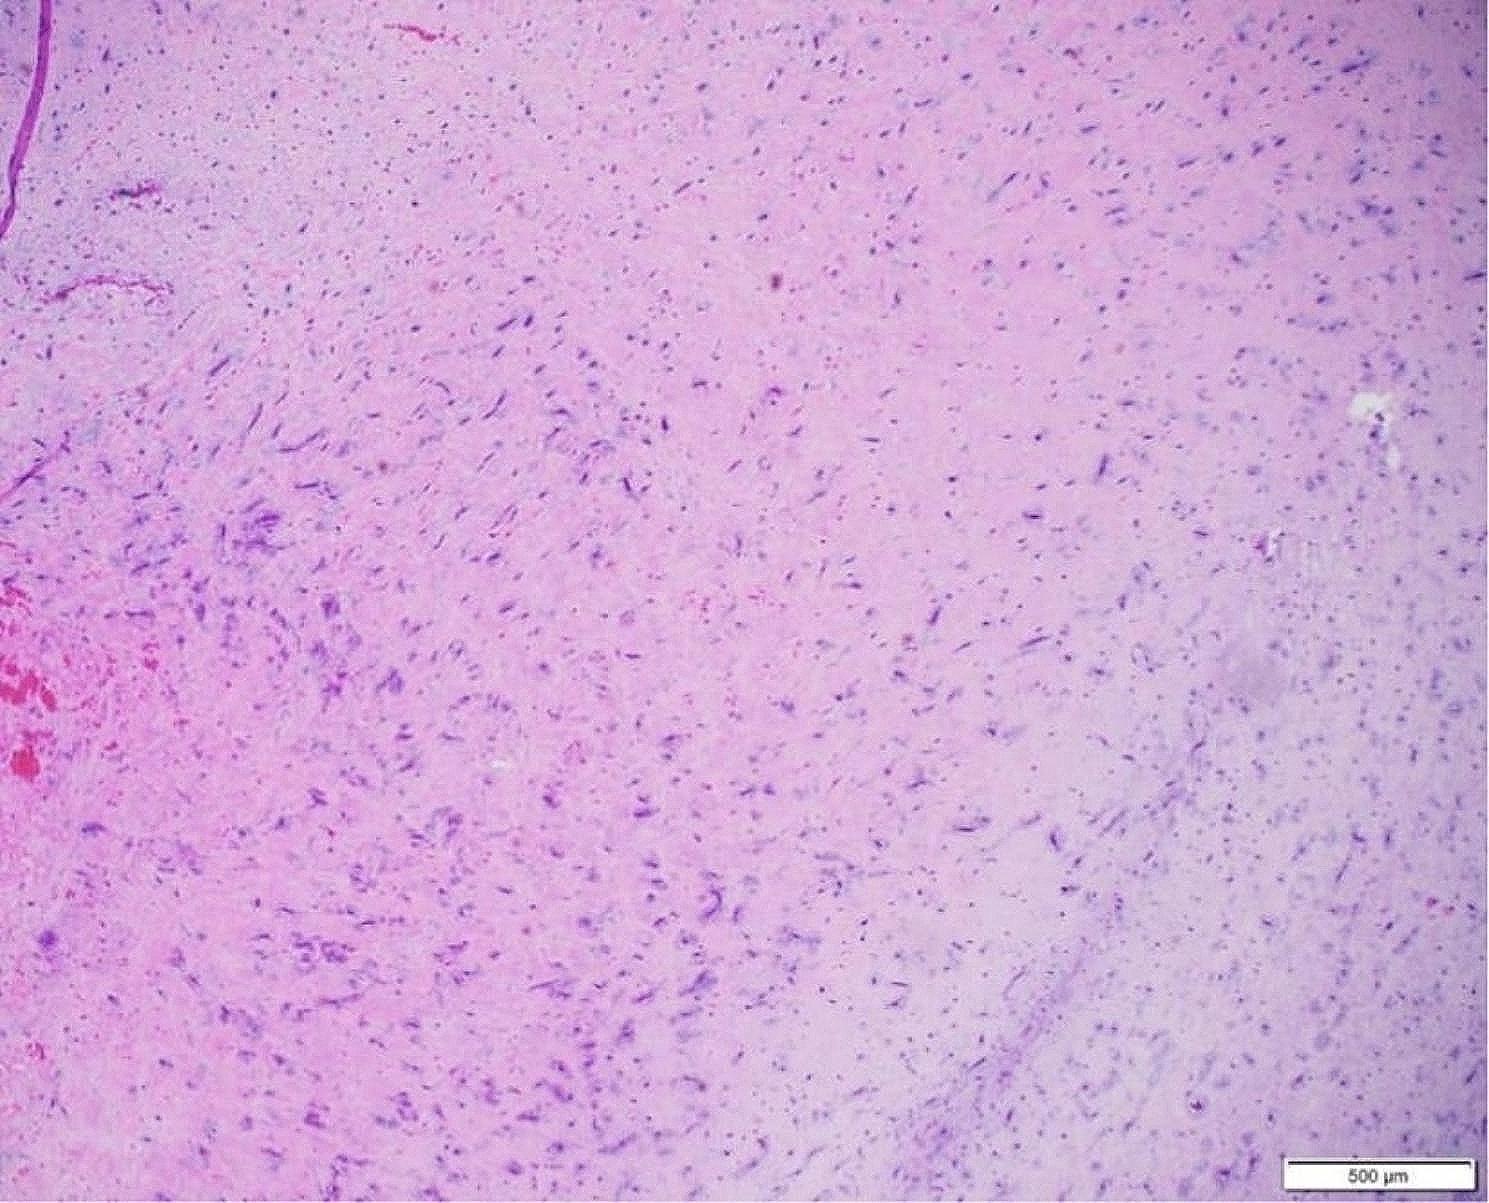

Atrial myxomas are typically found in the left atrium and are the most common among overall rare cardiac tumors. Herein, we describe the clinical course of a 72-year-old female with non-small cell lung adenocarcinoma found to have an atrial mass during an imaging for evaluation for lung cancer progression. Differentiating between distinct types of masses can pose a challenge to the treatment team especially in the setting of exiting malignancy. This case demonstrates the complex decision making involved in the diagnosis, and timing of intervention to remove atrial mass in patients with frailty and a fast-growing cardiac mass.

心房黏液瘤通常位于左心房,是总体罕见心脏肿瘤中最常见的类型。在此,我们描述了一名72岁女性非小细胞肺腺癌患者的临床病程,该患者在评估肺癌进展的影像学检查中发现有心房肿物。区分不同类型的肿物对治疗团队来说可能是一项挑战,尤其是在存在恶性肿瘤的情况下。本病例展示了在诊断以及对体弱且心脏肿物生长迅速的患者进行心房肿物切除干预时机方面所涉及的复杂决策。